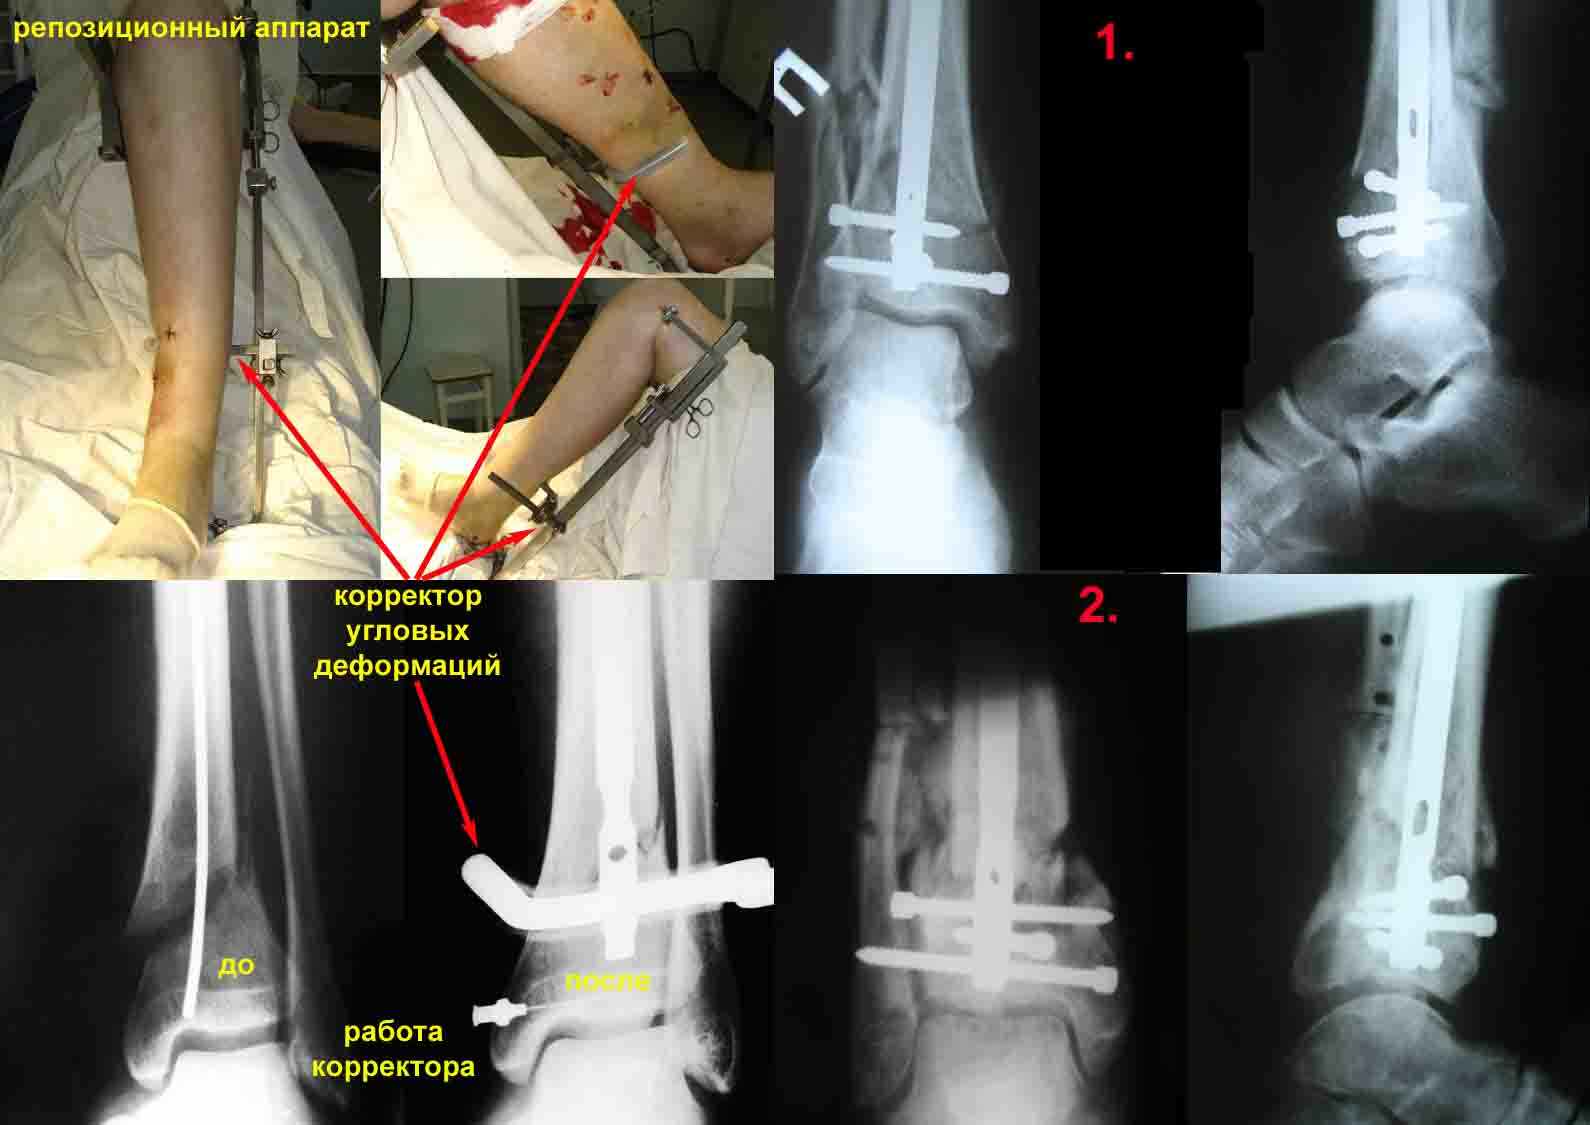

1. использование спицевого репозиционного аппарата для предварительной репозиция костных отломков на операционном столе и удержание костных отломков в репонированном положении на протяжении всего времени оперативного вмешательства.

Что касается конкретного случая. Перелом инфраистмальный, поэтому чрезмерно рассверливать канал и вводить стержень максимально возможного диаметра бессмысленно. В дистальном отломке он всё равно плотно сидеть не будет. Репозиция костных отломков должна быть обеспечена до введения стержня с помощью спицевого репозиционного аппарата. Нужен именно репозиционный (а не только дистракционный) аппарат, так как после дистракции ожидайте появления наружной угловой деформации в месте перелома, которую до введения стержня тоже необходимо устранить. Если устранены все виды угловых деформаций, нет никакой необходимости в применении отклоняющих спиц и винтов Poller. Стержень точно войдёт в центр дистального отломка. Вообще считаю применение винтов Poller при инфраистмальных преломах необоснованным, трудоёмким и малопродуктивным занятием. Стержень необходимо вводить максимально глубоко (0,5 см до суставной поверхности большеберцовой кости). Такое глубокое погружение стержня обеспечит Вам ширину маневра при дистальном блокировании. Сколько и в каких плоскостях вводить блокирующие винты на дистальном конце стержня? Это зависит от конструкции стержня и формы блокирующих отверстий на дистальном конце стержня. Если все блокирующие отверстия на дистальном конце стержня круглые и расстояние между отверстиями во фронтальной плоскости стандартное (30 мм и меньше), то при данном уровне перелома и максимальном погружении стержня, небольшом расстоянии от конца стержня до самого дистального из блокирующих отверстий (0,5-0,7 см) будет достаточно и двух винтов во фронтальной плоскости. В Вашем случае они разместятся в дистальном отломке. Если одно из блокирующих отверстий на дистальном конце стержня во фронтальной плоскости овальное (ChM, предназначено для дистальной динамизации), необходимо введение как минимум двух винтов в круглые отверстия во взаимно перпендикулярных плоскостях.

Для примера – вложенный файл. Фотографии репозиционного аппарата и работа корректора угловых деформаций.

Механическое прицельное устройство для дистального блокирования предназначенное для проведения блокирующих винтов канюлированных стержней в разных плоскостях без ЭОПа (и вообще без применения рентгентехники) с успехом применяется нами, на протяжении вот уже десяти лет. (Рентгенограммы 1 и 2)